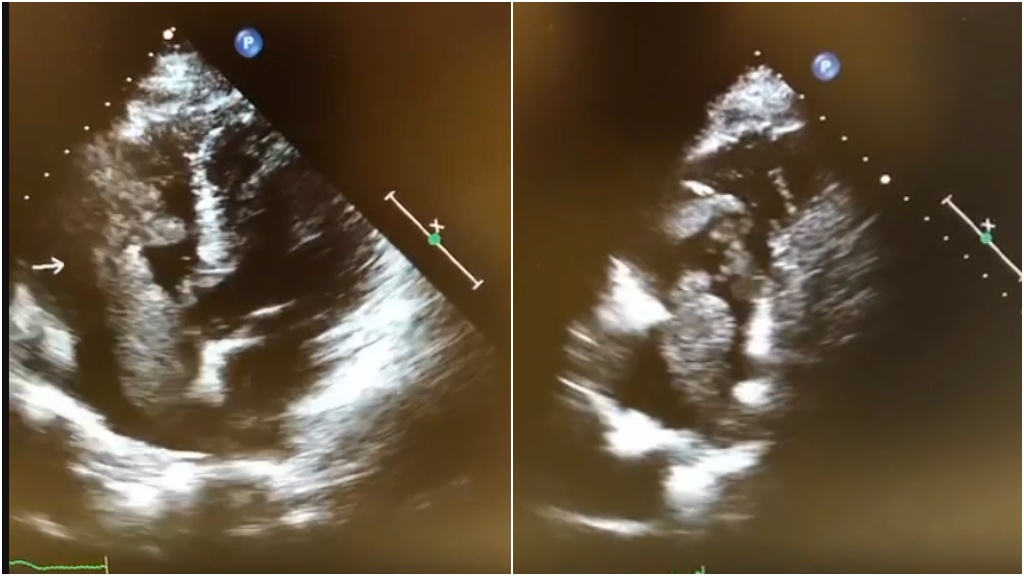

林謂文說明,如果心臟腫瘤非常大,可能會塞住心臟內的通道,造成心因性休克或阻塞性休克,導致病人猝死。他強調,若病人出現相關症狀,其實不難診斷心臟腫瘤。只要安排心臟超音波檢查,就可以清楚看到心臟內有腫瘤在滑動。

位於左心室或左心房的腫瘤,大多是良性的黏液瘤,惡性腫瘤則非常罕見。治療心臟腫瘤唯有透過外科開心手術將腫瘤完整切除,並送往化驗,才能確定是良性還是惡性。